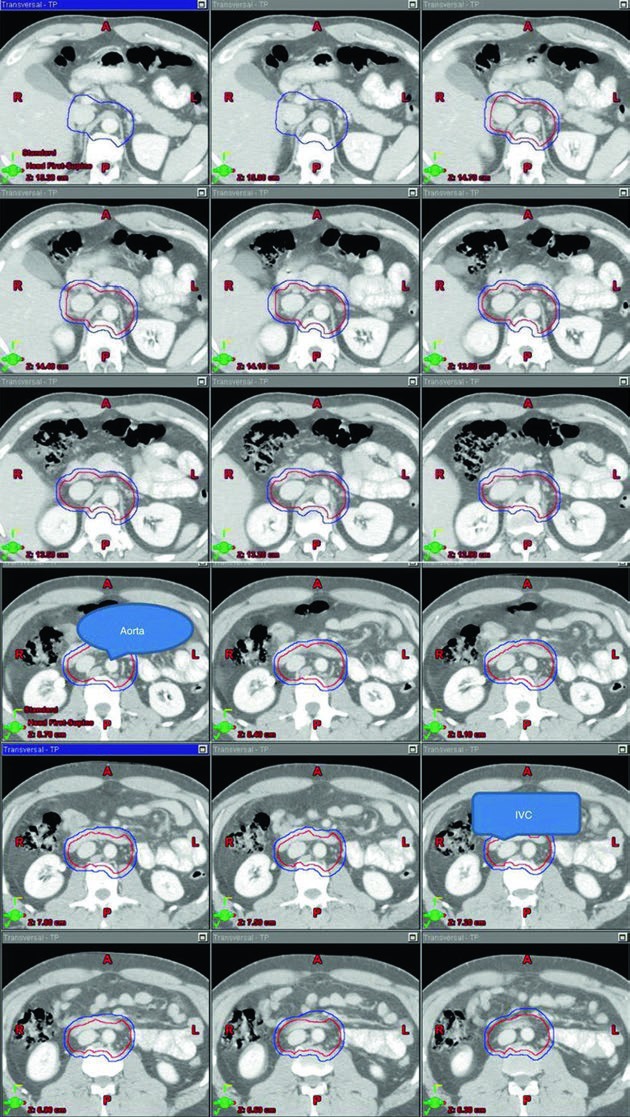

As figuras do capítulo ajudam porque mostram o volume organizado sobre a anatomia vascular, não apenas como um desenho abstrato. Na sequência superior-inferior do estágio I, o leitor enxerga como cava inferior e aorta funcionam como eixo geométrico do contorno, e isso conversa diretamente com a tabela de volumes. O valor dessa apresentação está em ligar cartografia linfonodal, marcos anatômicos e limites de bloco em uma mesma lógica.

Quando a radioterapia é escolhida nesse contexto, o alvo recomendado é a cadeia para-aórtica isolada, o clássico PA strip, a menos que tenha ocorrido violação inguinal ou escrotal prévia. A dose descrita no capítulo para o PTV fica entre 20 e 25,5 Gy, com frações de 1,5 a 2,0 Gy. Essa faixa de dose não aparece solta: ela vem anexada a uma definição de CTV baseada em vasos e a marcos anatômicos concretos, o que ajuda a manter coerência entre indicação e geometria.

O CTV do estágio I parte do contorno da cava inferior e da aorta desde 2 cm abaixo do topo do rim, superiormente, até a bifurcação dos vasos ilíacos, inferiormente. Depois, a cava recebe expansão de 1,2 cm e a aorta recebe expansão de 1,9 cm. Os dois volumes são combinados, e então se subtraem osso, músculo e alça intestinal. Esse detalhe é importante porque mostra que o capítulo não descreve apenas “onde cobrir”, mas também onde recuar para respeitar anatomia normal. Na sequência, o volume final é expandido em 0,5 cm mais 0,7 cm até a borda do bloco para formar o PTV.

Os marcos anatômicos completam a definição. O limite superior fica no topo de T11, com observação de que algumas fontes recomendam topo de T12. O limite inferior fica na base de L5. Lateralmente, o campo vai até a borda dos processos transversos, tipicamente em largura de cerca de 10 cm. Para seminoma à esquerda, os estudos de mapeamento nodal citados no capítulo sugerem que cobrir o hilo renal esquerdo pode ser opcional. Esse “pode ser opcional” é o tipo de nuance que vale ouro: não é omissão, é escolha deliberada ancorada em topografia.

Tabela 27.1. Volumes sugeridos para seminoma testicular estágio I

A tabela abaixo resume exatamente como o capítulo combina anatomia vascular, limites ósseos e dose no cenário adjuvante do estágio I. Ela funciona como ponte entre a descrição textual e a figura do PA strip.

| Volume-alvo | Definição baseada em TC e anatomia vascular | Definição baseada em marcos anatômicos |

|---|---|---|

| CTV | Contornar cava inferior e aorta desde 2 cm abaixo do topo do rim, superiormente, até a bifurcação dos vasos ilíacos, inferiormente. Expandir a cava inferior em 1,2 cm e a aorta em 1,9 cm. Combinar os dois volumes e subtrair osso, músculo e intestino. |

Borda superior: topo de T11 (algumas fontes recomendam topo de T12) [6]. Borda inferior: base de L5. Bordas laterais: margem dos processos transversos, tipicamente cerca de 10 cm de largura. |

| PTV 20–25,5 Gy em 1,5–2,0 Gy por fração |

Expandir o CTV final em 0,5 cm + 0,7 cm até a borda do bloco. | Para seminoma à esquerda, os estudos de mapeamento nodal sugerem que cobrir o hilo renal esquerdo é opcional [7]. |

Fonte: Target Volume Delineation and Field Setup, 2nd Edition (Table 27.1).

Essa tabela deixa o cenário do estágio I bastante claro. Não se trata de irradiar “o retroperitônio” de maneira vaga; trata-se de um volume para-aórtico cuidadosamente delimitado, selecionado para pacientes específicos, com dose moderada e dependente da ausência de violação inguinal ou escrotal. Em um capítulo curto, é talvez o melhor exemplo de como indicação e técnica andam juntas.